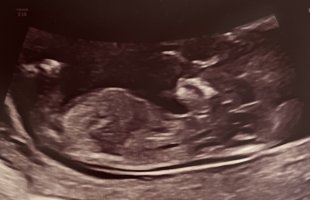

Tatt i uke 12. Noen tanker om kjønn?

følelsen er helt 50/50 nå